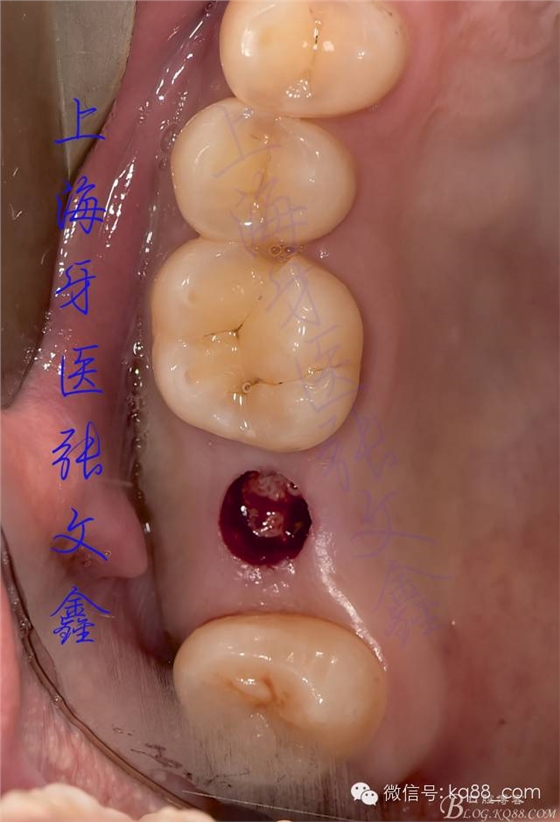

術前口內的照片